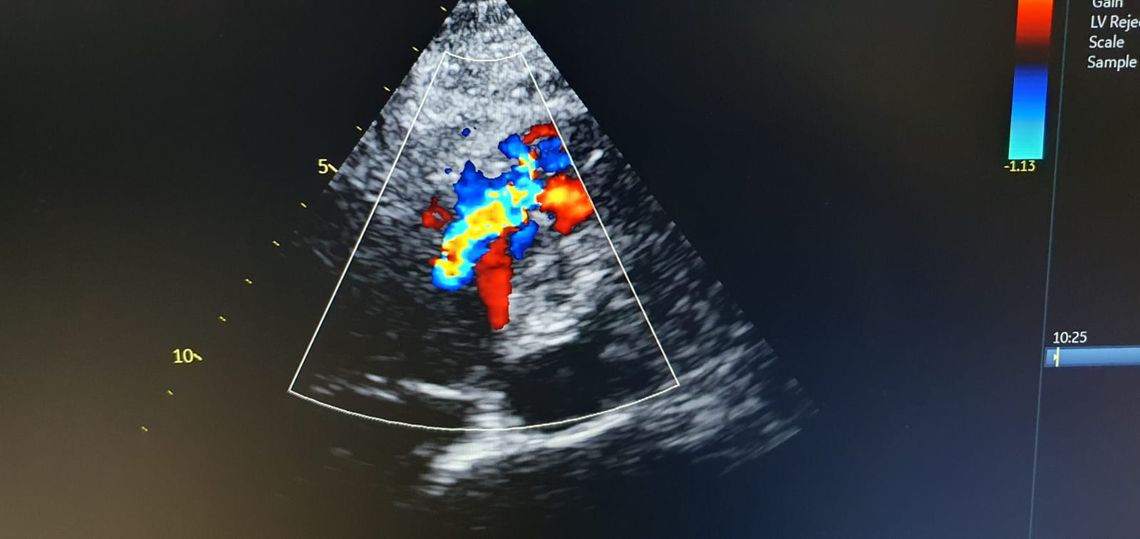

Zabieg przeprowadzili dr n. med. Maciej Chojnicki oraz prof. Marek Koziński, wspierani przez zespół specjalistów, w tym lek. Piotra Budę, lek. Agatę Polańską-Szczap, którzy odpowiedzialni byli za echokardiografię, oraz pielęgniarki Ewa Erdmann i Lidia Trzos, a także technika elektroradiologii Katarzynę Kościerską. Po zabiegu pacjentka trafiła na Intensywny Nadzór Kardiologiczny, gdzie opiekę nad nią sprawowała lek. Magdalena Tulińska.

Wstępne wyniki pokazują znaczną poprawę stanu pacjentki oraz jej parametrów echokardiograficznych. Planowane jest szybkie wypisanie jej do domu, co stanowi dużą nadzieję na pełne wyzdrowienie. Zespół medyczny szpitala wykazał się dużą wiedzą i umiejętnościami w przeprowadzeniu tego trudnego, rzadko stosowanego zabiegu, który daje pacjentce szansę na lepszą jakość życia.